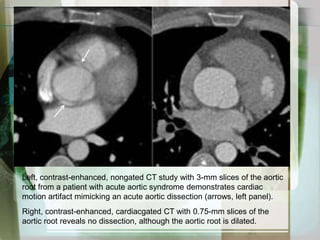

Left, contrast-enhanced, nongatedCT study with 3-mm slices of the aortic root from a patient with acute aortic syndrome demonstrates cardiac motion artifact mimicking an acute aortic dissection (arrows, left panel). Right, contrast-enhanced, cardiacgated CT with 0.75-mm slices of the aortic root reveals no dissection, although the aortic root is dilated.

Left, contrast-enhanced, nongatedCTstudy with 3-mm slices of the aortic root from a patient with acute aortic syndrome demonstrates cardiac motion artifact mimicking an acute aortic dissection (arrows, left panel). Right, contrast-enhanced, cardiacgated CT with 0.75-mm slices of the aortic root reveals no dissection, although the aortic root is dilated.